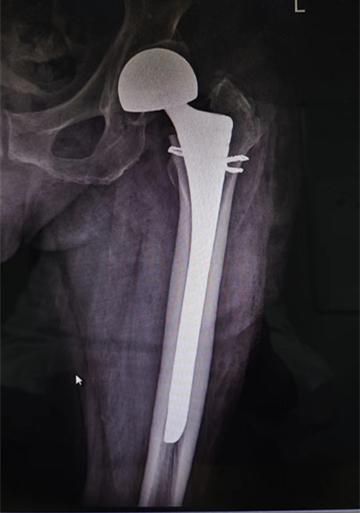

86、88、90、92、93、97、98,您以為這是一串考試成績(jī)嗎?不是,這是一個(gè)月內(nèi)我院關(guān)節(jié)外科、創(chuàng)傷骨科收治的10余名高齡患者的年齡,均為髖部骨折。通過(guò)關(guān)節(jié)外科、創(chuàng)傷骨科與麻醉科、心內(nèi)科、呼吸科、神經(jīng)內(nèi)科等兄弟科室的通力合作,均行手術(shù)治療,目前都已康復(fù)出院,戰(zhàn)勝了“人生最后一次骨折”,也獲得了患者家屬的高度贊譽(yù)。

臨床上,人生最后一次骨折,常常指的是老年人的髖關(guān)節(jié)骨折。由于骨質(zhì)疏松癥的發(fā)病率很高,根據(jù)資料統(tǒng)計(jì),男性一生中發(fā)生髖部骨折的風(fēng)險(xiǎn)高達(dá)11.2%,女性更高達(dá)23%。髖部骨折是對(duì)老年人影響最大的一類骨質(zhì)疏松骨折。不像那些發(fā)生在腕部或肩部的骨折,髖部骨折帶來(lái)的疼痛和下肢活動(dòng)障礙會(huì)迫使病人臥床,難以活動(dòng);而保守治療需要臥床三個(gè)月左右,而臥床帶來(lái)的四大并發(fā)癥,呼吸系統(tǒng)感染、泌尿系統(tǒng)感染、深靜脈血栓和褥瘡,哪一個(gè)發(fā)生了都會(huì)危及病人的生命。所以一旦發(fā)生髖部骨折,即使保守治療也會(huì)危險(xiǎn)重重,手術(shù)又有一定的風(fēng)險(xiǎn)。因此,髖部骨折在過(guò)去就被稱為“人生最后一次骨折”。手術(shù)治療可早期下地活動(dòng),但手術(shù)風(fēng)險(xiǎn)較高,存在心腦血管意外可能性較大。因此,術(shù)前需認(rèn)真進(jìn)行評(píng)估,盡可能降低手術(shù)風(fēng)險(xiǎn)。

隨著醫(yī)學(xué)技術(shù)的發(fā)展,髖部骨折手術(shù)治療已經(jīng)是比較成熟的手術(shù),高齡已不再是手術(shù)禁忌。老年人摔倒后應(yīng)積極就醫(yī),避免延誤最佳治療時(shí)機(jī)。